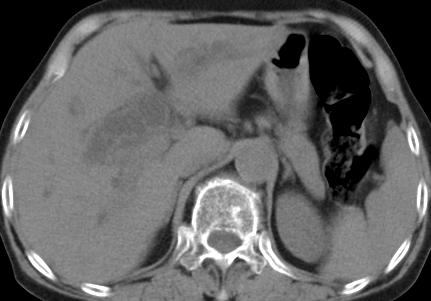

以下是引用齐原在2006-11-8 23:21:00的发言:[br]肝脏体积增大.肝表凸凹不平,肝内胆管扩张,胆总管扩张,胆总管末端突然截断,胰腺勾突增大,形态不规则.胰管扩张.考虑胰头癌.并低位梗阻性胆系扩张,胆囊炎.脾大.建议增强

以下是引用dyqct在2006-11-9 9:14:00的发言:[br]肝大,表面呈波浪状,肝内外胆管扩张,胆总管下端腔内见小结节状等密度影,胰管轻度扩张。胆囊显示不清。[br]考虑:1、胆总管下端占位性病变(等密度结石?壶腹部肿瘤?);[br] 2、肝硬化?[br] 3、建议增强扫描进一步检查。